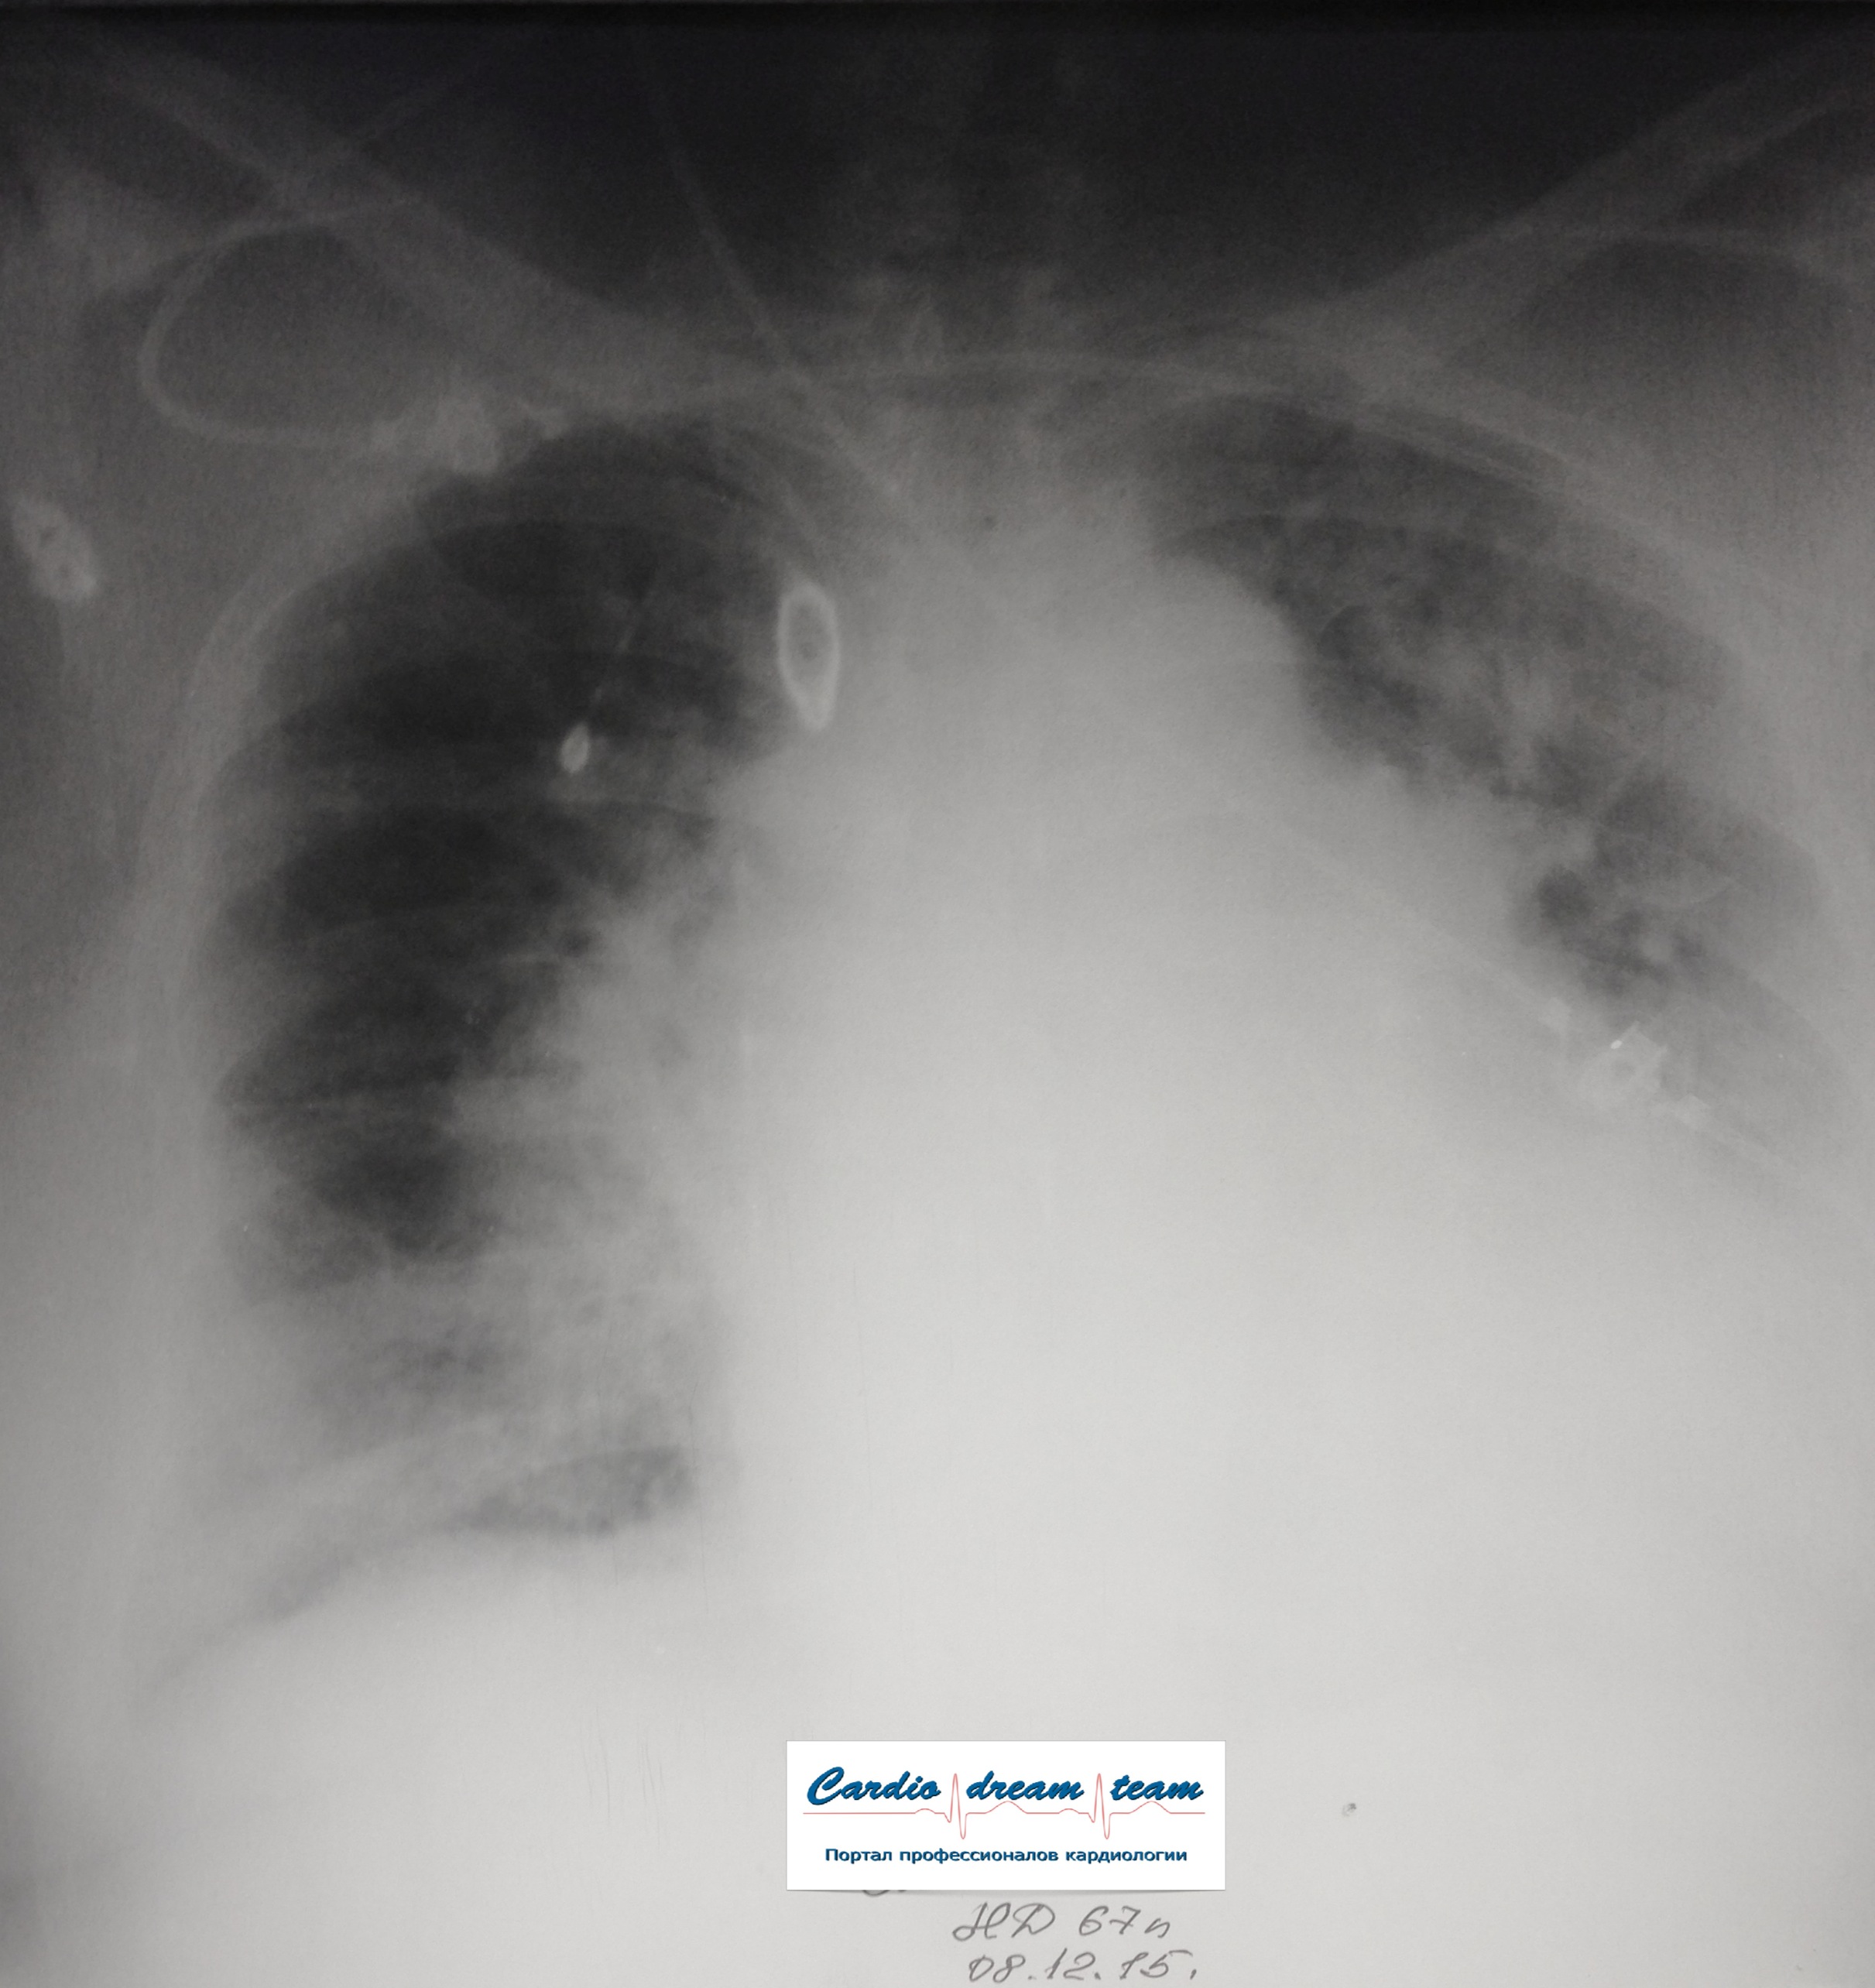

Не обсуждалась Дата 23-ИЮЛ-15 ОПИСАНИЕ: Проведена рентгенография органов грудной клетки в прямой проекции, положение лежа, условия ПИТ Легочные поля: неравномерно прозрачны за счет сосудистого обогащения, в базальных отделах с обеих сторон, отмечается сгущение легочного рисунка, за счет гиповентиляции, в плевральных полостях жидкость Легочный рисунок: Изменен по смешанному типу: обогащен за счет сосудистого компонента, деформирован за счет склероза. Корни: бесструктурны, расширены за счет сосудистого компонента, обогащены Синусы: определяется наличие жидкости по линии 5 ребра Сердце: широко лежит на диафрагме отмечается расширение границ сердечной тени влево, вправо экг-электроды. ЗАКЛЮЧЕНИЕ: Рентген-признаки 2-х стороннего гидроторакса с гиповентиляцией базальных сегментов.. Признаки застоя по МКК 2 степени (умеренно выраженный). Пневмосклероз. Р-признаки гипертрофии левого желудочка сердца. Склероз аорты.